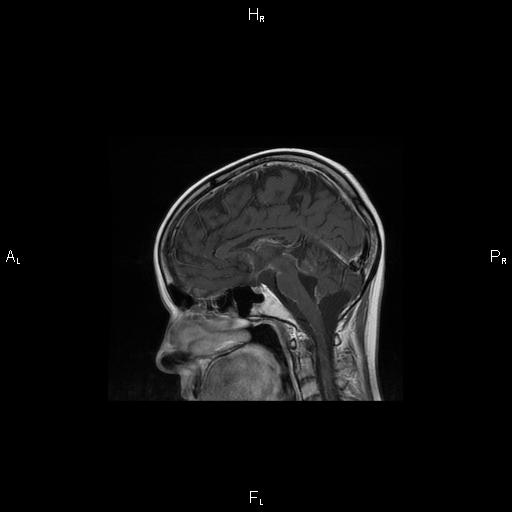

6. Рис. 2а

Тема

Тип Материалы исследования

Посмотреть (28KB)

Метаданные ▾

7. Рис. 2б

Посмотреть (33KB)